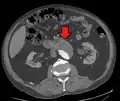

An axial contrast-enhanced CT scan demonstrating an abdominal aortic aneurysm of 4.8 by 3.8 cm